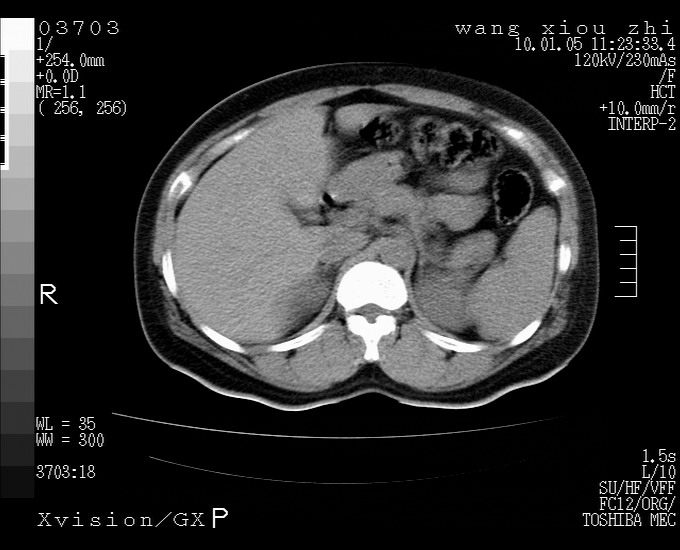

标题: CT23996:f,40.B超提示肿物。

左肾体积增大!下极见一密度略高团状软组织影!肾周结构组织未见明显异常!考虑左肾占位!建议增强!病史?

左肾占位性病变,建议增强。

左肾占位性病变,考虑肾癌,建议增强 。

左肾占位,肾门及腹膜后淋巴结肿大,考虑透明细胞癌可能性大,建议增强

左肾体积增大,内见肿块影,考虑占位,建议增强。